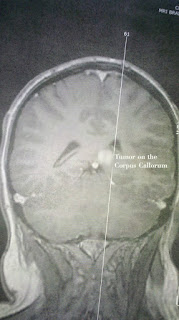

Brain Tumors and Neurofibromatosis

We have two little friends, that came into our lives in 2010. We never could have imagined how close we would become. In 2012...We plan on saying goodbye to these friends!